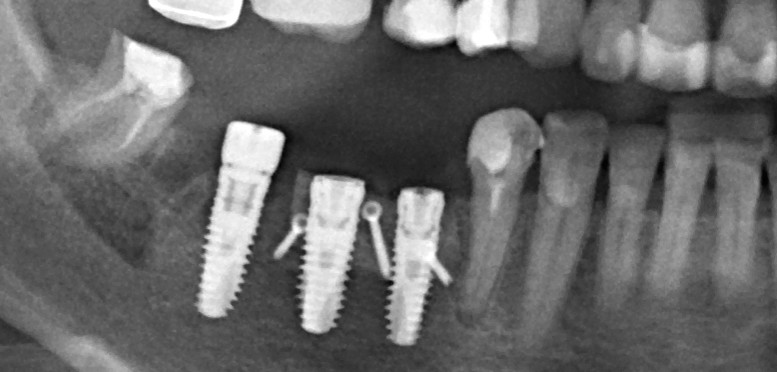

Почему всё это должен знать имплантолог? Дело в том, что суммарная длина конструкции «имплантат-абатмент-коронка» должна оставаться неизменной, если мы хотим, чтобы коронка была в прикусе и нормально функционировала. Это значит, что небольшая длина импланта должна быть компенсирована раздутым эго и большим джипом увеличением размеров супраструктуры, а именно — абатмента и коронки:

Другими словами, нагрузка в 30 Н, приложенная к коронке в точке А, в точке B , будет равняться 90 Н, при условии, что соотношение имплантат/супраструктура будет как 1:3:

А это это уже, как вы понимаете, немаленькая цифра. Например, момент силы при затяжке болтов колёс большинства автомобилей составляет 100-120 Нм, что, согласитесь, ненамного больше.

И, может быть, имплантату на это пофиг, остеоинтеграция позволяет и не такое. Но как насчет соединения имплантат-абатмент? Особенно, при отсутствии антиротационных элементов и соединяющих винтов на имплантах Bicon? Уверен, по этому поводу тоже есть какое-то научное исследование и, скорее всего, оно тоже утверждает, что «усё нормуль», но, опять же, Архимед…. физика…. простая механика… Извините, но как-то это не укладывается у меня в голове.